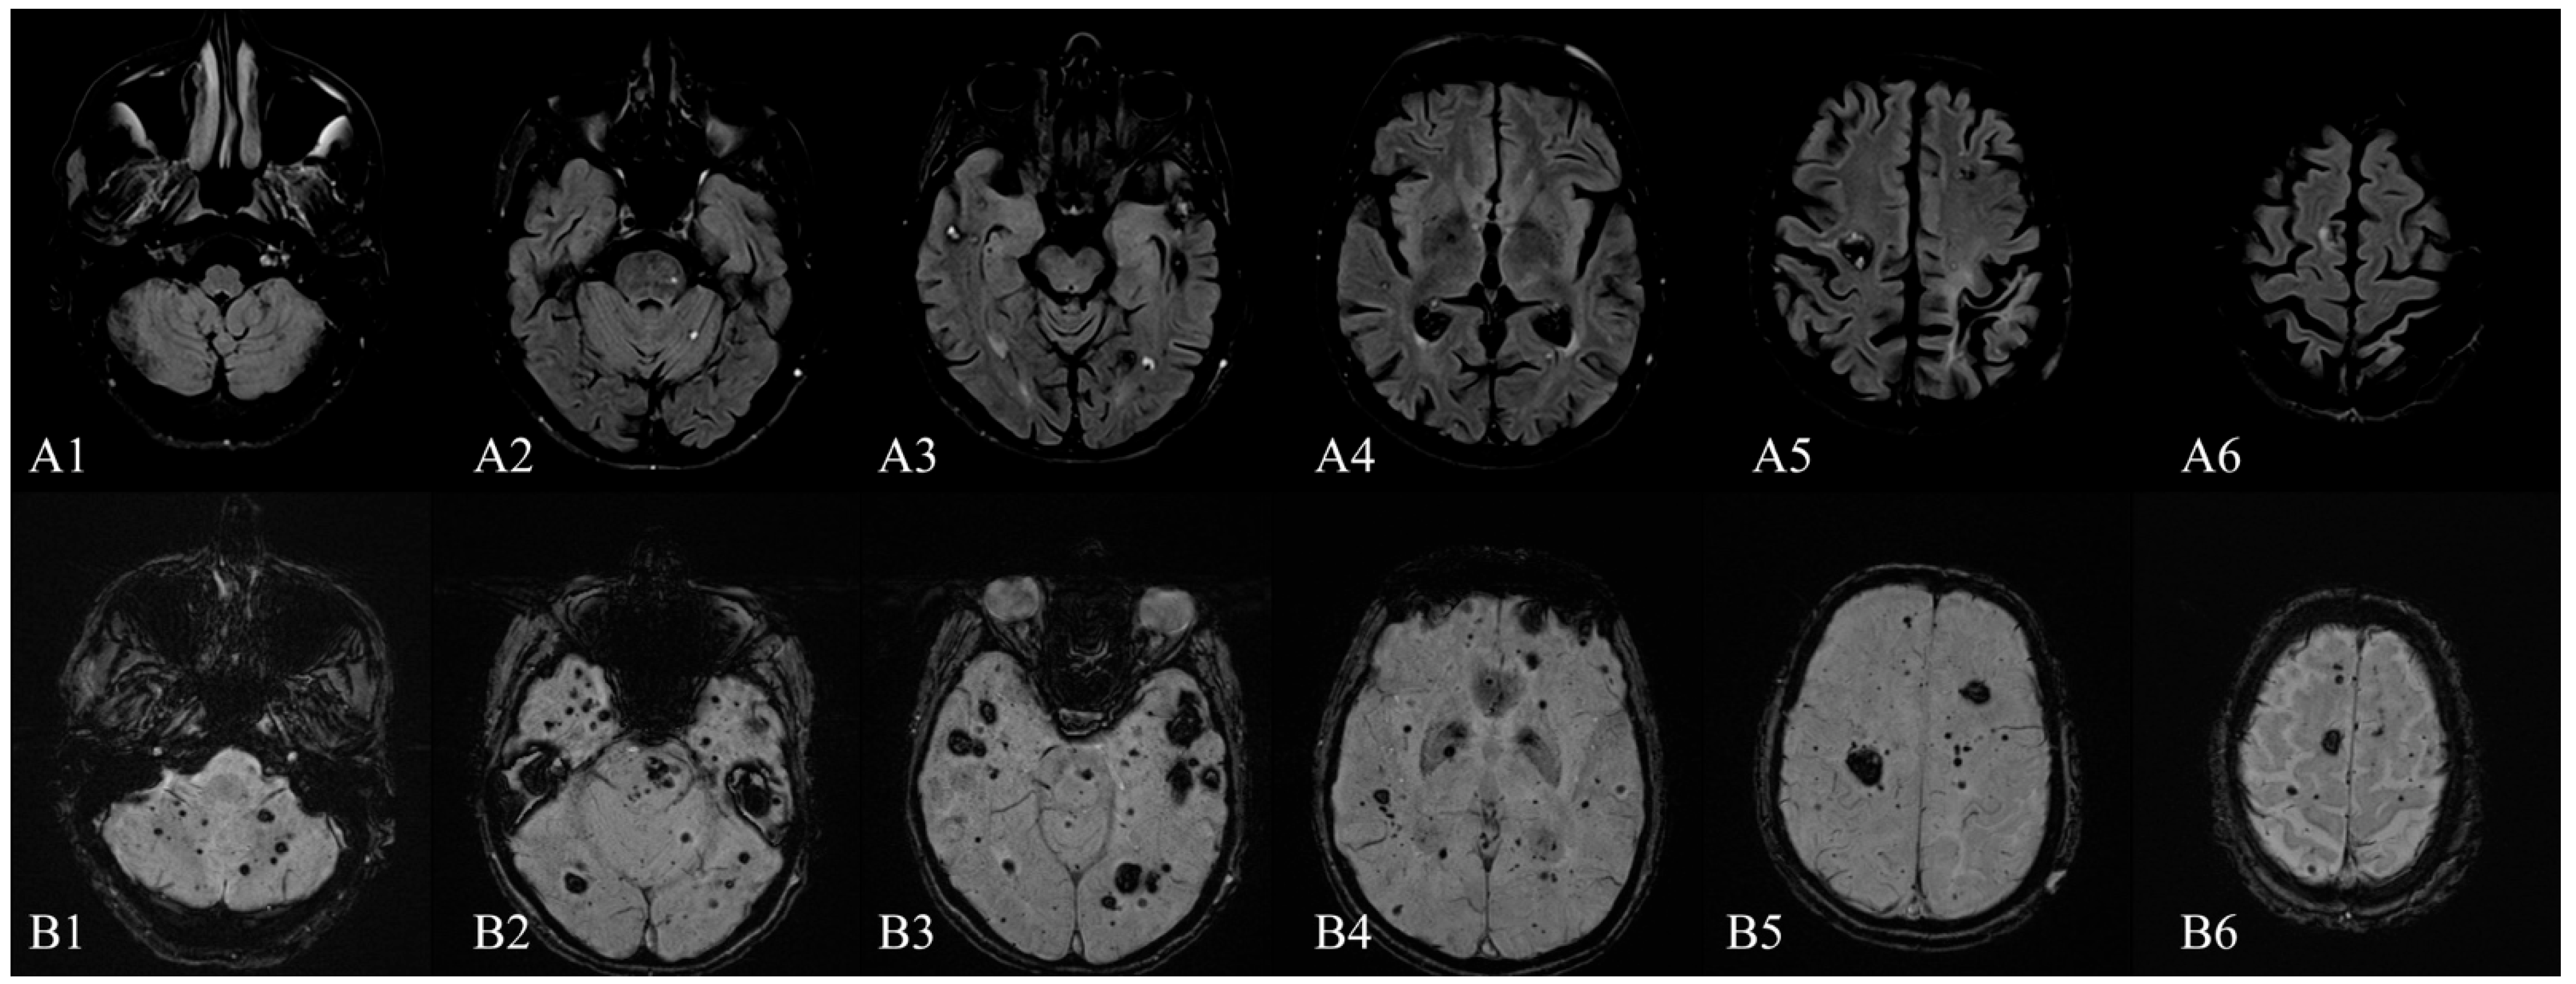

Magnetic Resonance Imaging of Multiple Cerebral and Spinal Cavernous Malformations of a Patient with Dementia and Tetraparesis

Antonescu, F.; Butnariu, I.; Cojocaru, F.M.; Anghel, D.N.; Antonescu-Ghelmez, D.; Tuță, S. Magnetic Resonance Imaging of Multiple Cerebral and Spinal Cavernous Malformations of a Patient with Dementia and Tetraparesis. Diagnostics 2022, 12, 677. https://doi.org/10.3390/diagnostics12030677